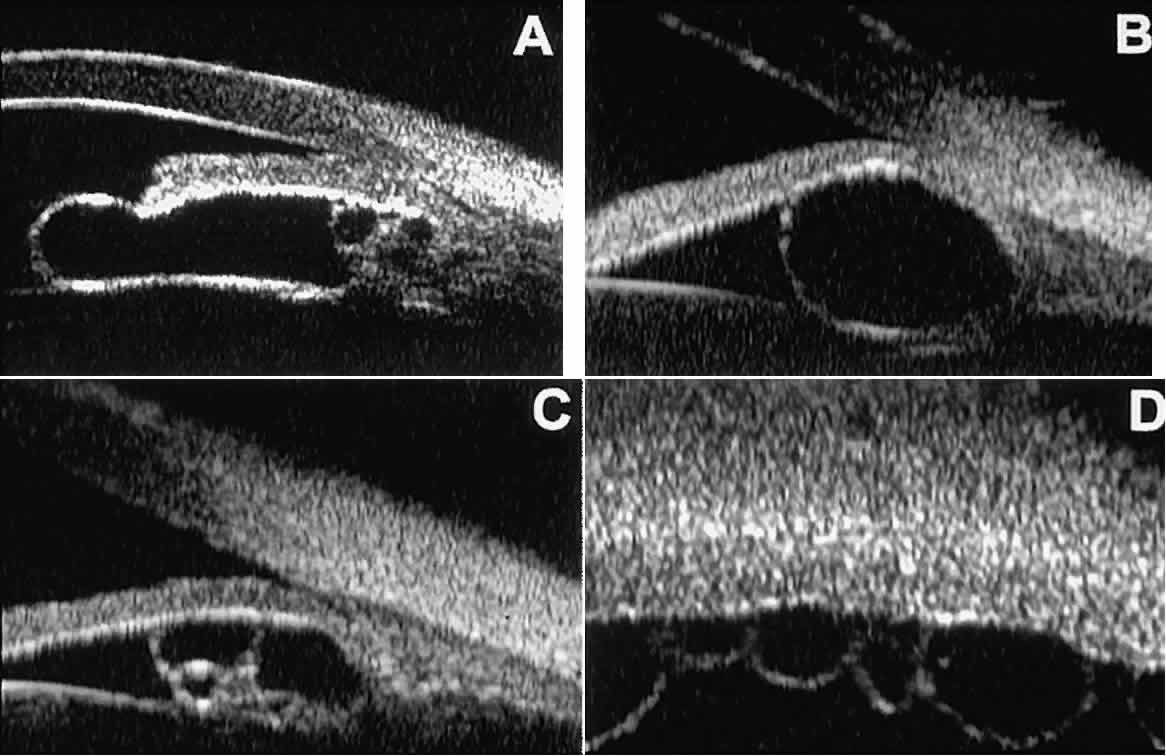

In eyes with a narrow angle, UBM shows the extent of angle closure, reveals

the depth of the anterior and posterior chambers, and identifies

pathologic processes pushing the lens and iris forward (Fig. 11).2–4,8 UBM has been able to differentiate between primary angle closure (i.e., cases of angle closure without additional pathology responsible for the

anterior lens-iris displacement [see Fig. 11A] and secondary angle closure due to processes such as lens swelling

and dislocation (see Fig. 11B), massive hemorrhagic retinal detachment pushing the lens and iris anteriorly (see Fig. 11C), and multiple neuroepithelial cysts of the iridociliary sulcus (see Fig. 11D).  Fig. 11. Angle configuration in eyes with angle-closure glaucoma. A. Primary angle-closure glaucoma with anterior displacement of lens and

iris. B. Angle closure secondary to swollen, cataractous lens (phakomorphic angle

closure). C. Angle closure secondary to massive hemorrhagic retinal detachment; the

subretinal blood is evident in the lower right corner of the photograph. D. Angle closure secondary to multiple peripheral iris cysts. Fig. 11. Angle configuration in eyes with angle-closure glaucoma. A. Primary angle-closure glaucoma with anterior displacement of lens and

iris. B. Angle closure secondary to swollen, cataractous lens (phakomorphic angle

closure). C. Angle closure secondary to massive hemorrhagic retinal detachment; the

subretinal blood is evident in the lower right corner of the photograph. D. Angle closure secondary to multiple peripheral iris cysts.

|